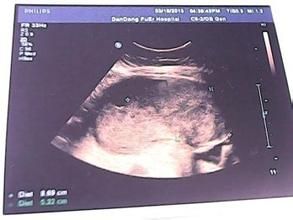

胎盤血竇,也稱為胎盤靜脈池(血池),指在胎盤絨毛中心部分無絨毛處,胎盤實質中的較大的近圓形暗區,可見細密光點從側壁流入暗區內。